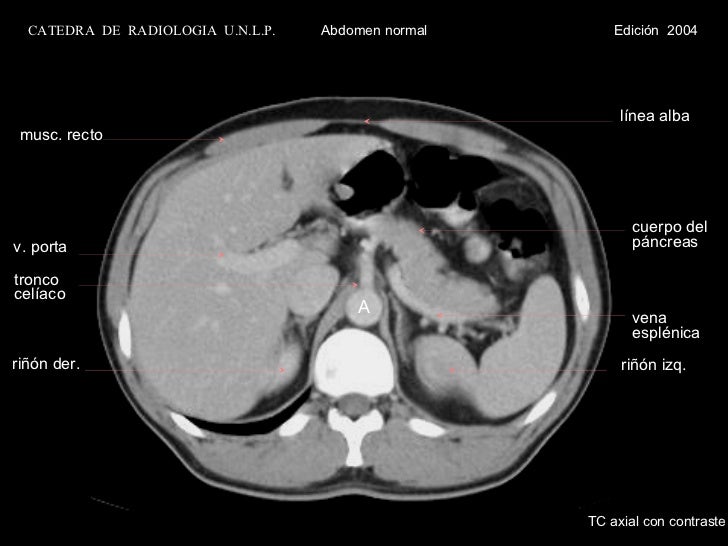

Tac abdominal con contraste. Abdomen Por lo general, este examen se realiza con el fin de diagnosticar la causa de dolor abdominal y enfermedades intestinales de colon La exploración por TAC del abdomen / pelvis también se realiza para Visualizar el hígado, el bazo, el páncreas, la próstata y los riñones, entre otros. Tomografia Tomografia Axial Tomografia Torax en Caracas Tomografía, Tomografía de Abdomen y Pelvis, Tomografía con Doble Contraste, TAC de Cráneo, Angiotac, Urotac, TAC de Senos Paranasales Axiales y Coronales, Angiotac Coronario, Tomografía con Reconstrucción Volumétrica, Broncoscopia Virtual, Mamografía, Mamografía con Implantes, Tomo Mamografía 3D, Co. Muchos pacientes también reciben un agente de contraste con yodo en forma intravenosa (inyectado en vena), para ayudar a evaluar los vasos sanguíneos y los órganos tales como el hígado, los riñones y el páncreas Cuando ingrese en el dispositivo de exploración por TAC, podría ver haces de luces especiales proyectados sobre su cuerpo.

TC do abdómen com contraste Na tomografia computorizada (TC) abdominal com contraste pretendese avaliar o comportamento vascular das estruturas em estudo Os produtos de contraste iodados (à base de iodo) são aplicados por via endovenosa e permitem ampliar o contraste entre as estruturas com distintos fluxos sanguíneos, sendo particularmente útil na avaliação das estruturas hipervascularizadas, como por exemplo tumores ou inflamações. Tac de abdomen o de abdomen y pelvis Con contraste endovenoso y, en algunos casos, contraste oral y endovenoso El tac de abdomen permite ver lesiones en cualquiera de los órganos abdominopelvianos, léase hígado, páncreas estómago, riñones, intestinos, vejiga, próstata, útero, ovarios, lesiones como tumores, quistes o seguimiento post quirúrgico de alguno de ellos. En muchas ocasiones, una tomografía computarizada del abdomen se realiza con una de la pelvis El examen debe tardar menos de 30 minutos Preparación para el examen Usted necesitará tener un colorante especial, llamado medio de contraste, en el cuerpo antes de algunos exámenes El medio de contraste ayuda a que ciertas áreas se vean mejor.

Servicios incluidos AngioTAC de la zona abdominal;. TC abdominal con contraste se lleva a cabo en función del tipo específico al que pertenece el escáner porque la investigación estándar en cualquier caso es menos precisa en comparación con un resfriado. El TAC Abdominal es la prueba idónea para una vista general del abdomen porque gracias a la administración de contraste se pueden valorar todas las estructuras abdominales El contraste es una sustancia líquida que puede ser administrada bebida o inyectada y ayuda a la visualización de estas partes del cuerpo proporcionando mayor información diagnóstica.